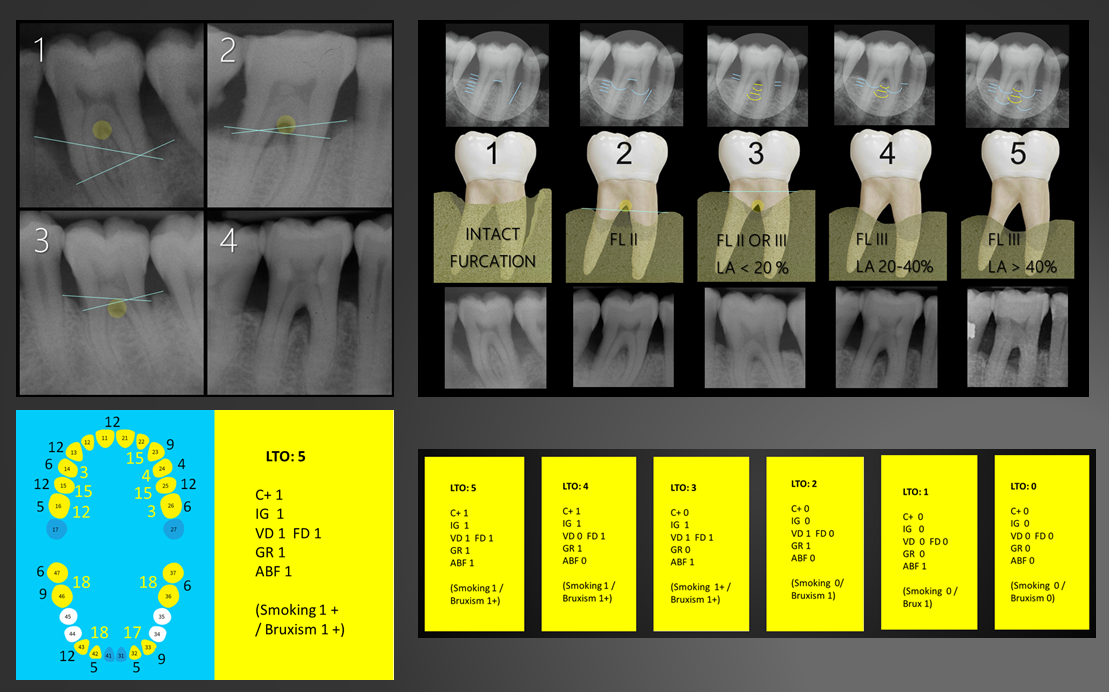

About twenty factors predictive of tooth loss were analysed using different statistical tests, searching for consistency of results. Eleven of these factors, most clearly associated with tooth loss, were finally selected to construct the predictive model.

The basic idea behind a predictive model is to obtain the probability of tooth loss as a value from 0 to 1, rather than using conventional prognostic categories, which are subjectively interpreted according to regression coefficients (e.g., p=0.0005). This probability value of tooth loss can also be associated with ranges of tooth survival expectancy, facilitating decision making.

PerioProject is not a tool capable of assuring which teeth will be lost and when, but it does give extreme values indicating a high probability that the tooth will be maintained (99% specificity) or lost, while estimating the survival expectancy for intermediate values, and thus providing real meaning to the conventional questionable prognosis category.